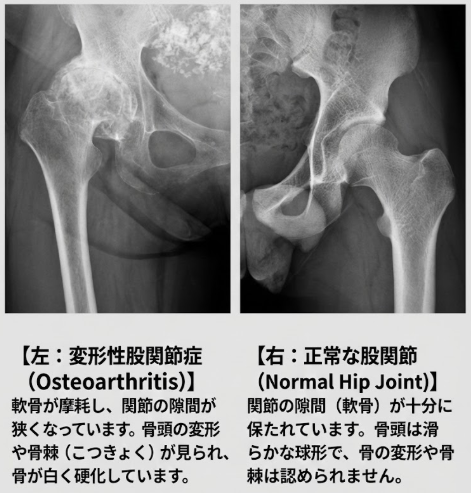

画像検査はX線が基本で、関節裂隙の狭小化、骨棘、骨硬化、骨嚢胞、寛骨臼や大腿骨頭の変形、両者の位置関係を確認します。必要に応じてCTで骨形態を詳細に評価し、MRIで早期の関節唇損傷や軟骨変性、関節水腫を把握します。なお、痛みが強いにもかかわらず画像変化が乏しい場合には、痛みの感じ方が過敏になる中枢性感作が関与している可能性も考慮します。

当院で施行したレントゲン:変形性股関節症と正常な股関節の比較